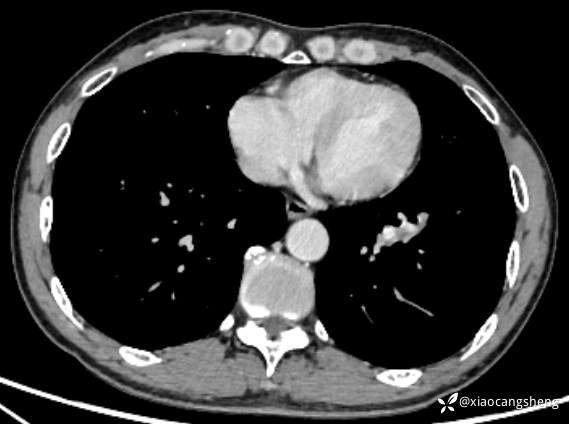

强化后纵膈窗

2023-11-03门诊复诊,院外未在痰中带血,复查胸部CT: